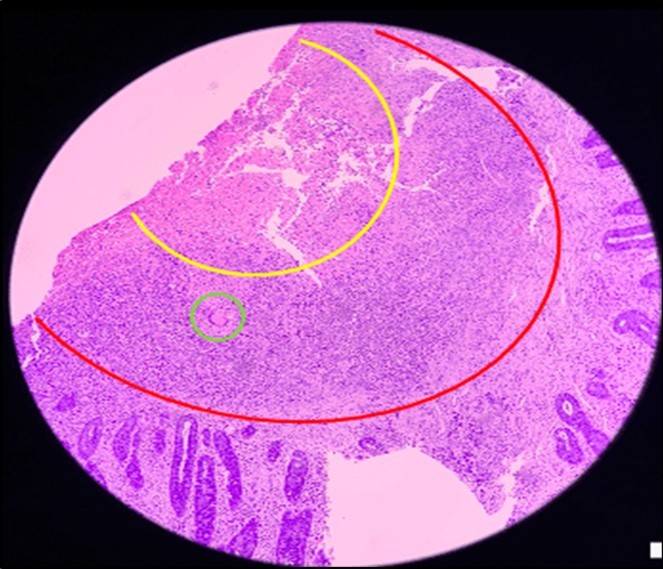

Biopsy showed chronic granulomatous inflammation with caseation necrosis and Langhan’s type giant cells consistent with tuberculous etiology (Figure 6, and Figure 7). TB PCR detected Mycobacterium tuberculosis, Rifampicin (MTB, RIF) resistance indeterminate. Category I Anti-TB treatment for six months was started and the service planned to repeat both colonoscopy and CT-scan after the initial round of anti-TB treatment. Currently, the patient is able to work with no abdominal pain and was able to tolerate her anti-TB drug regimen

Figure 6.Pathologic slide in the low power field. The area inside the yellow circle is the area of central necrosis. The portion inside the red circle is the peripheral lymphocytic ring, and inside the green circle is the Langhan’s type multinucleated giant cells

Pathologic slide in the low power field. The area inside the yellow circle is the area of central necrosis. The portion inside the red circle is the peripheral lymphocytic ring, and inside the green circle is the Langhan’s type multinucleated giant cells